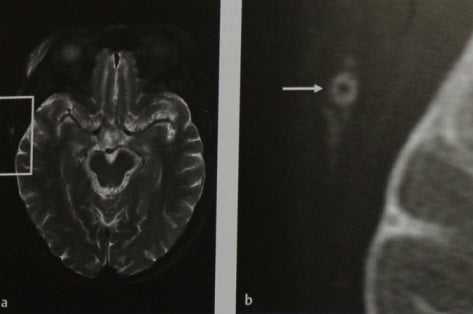

Гигантоклеточный артериит. МРТ в аксиальной проекции, а, b Визуализация с субтракцией сигнала от жировой ткани в Т2-взвешен- ном режиме. Вся окружность мозгового черепа визуализируется на уровне височной доли (а), поскольку это срез правой экстракраниальной височной области (b). Концентрическое утолщение стенки правой поверхностной височной артерии (стрелка) и отек окружающей паренхимы,

В проекции утолщенной артериальной стенки определяется выраженное гомогенное усиление.